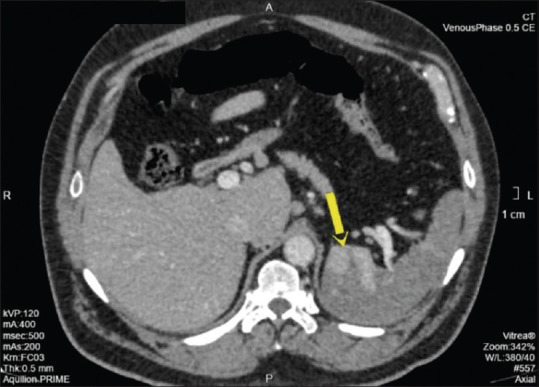

Mesenteric vascular thrombosis, typically of the superior mesenteric artery, is a frequent occurrence in patients with hypercoagulable conditions. Isolated involvement of the celiac artery is rare. Patients with celiac artery thrombosis can present with an acute abdomen or occasionally with acid peptic symptoms. A delay in diagnosis is associated with high rates of morbidity and mortality. We present a rare case of splenic infarction with celiac trunk thrombosis in a 54-year-old patient with underlying antiphospholipid (APLA) syndrome who presented with epigastric pain that was mistaken for symptoms of acid reflux.

Abstract Image